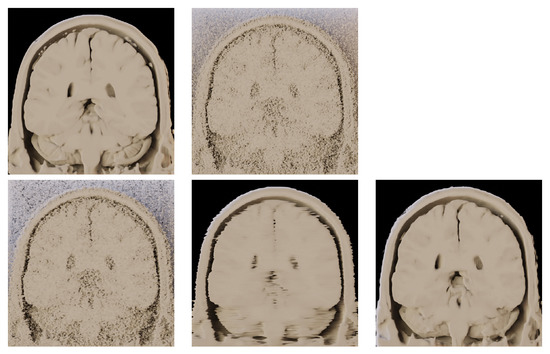

- Application of parallel version of BM4D algorithm to many-core architectures and combination of multi and many-core HW and proving the scalability tests.

- Comparison of the algorithm with DL-based approaches.

- Testing the algorithm as a pre-processing stage before volume rendering.